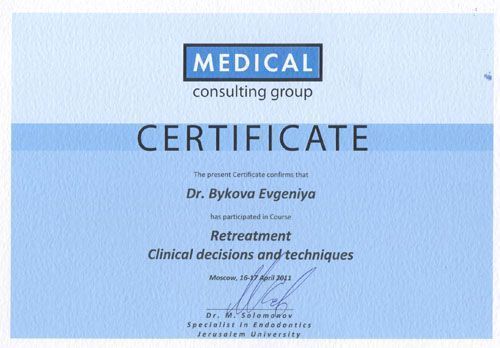

- Эксперт в сложной эндодонтии (нестандартная анатомия, перелечивание корневых канал)

Дополнительное образование

- 2013 Endo-Prosthodontic Relationship

- 2014 - X International Congress of VDW Endodontic Synergy GmbH

- 2014-2015 New topics and accents in Endodontics